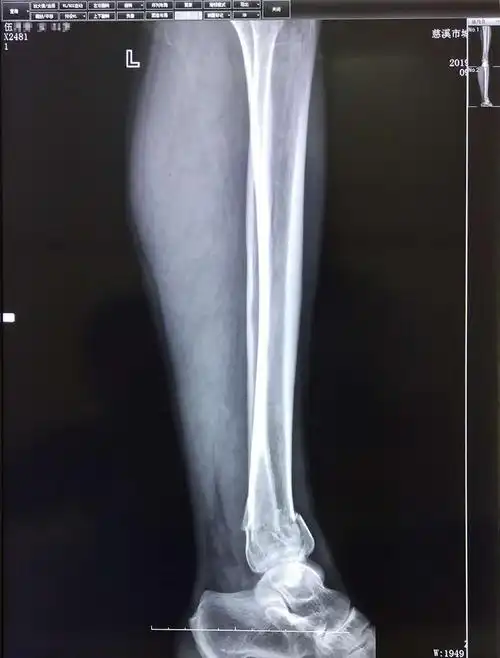

比较严重,不过经过检查,头脑没有什么问题,另外就是腿部有两处骨折

姜先生的腿部骨折躺在病床上.

孙培权医师杏林妙手成功使下腿双骨折错位患者康复

踝关节骨折l-h分型旋后外旋4度损伤病例分享 梁志军